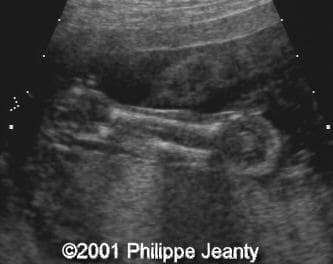

Note the striking cross-section of both lower legs with absence of the fibula on the right leg (left on the images):

clip0006

clip0007